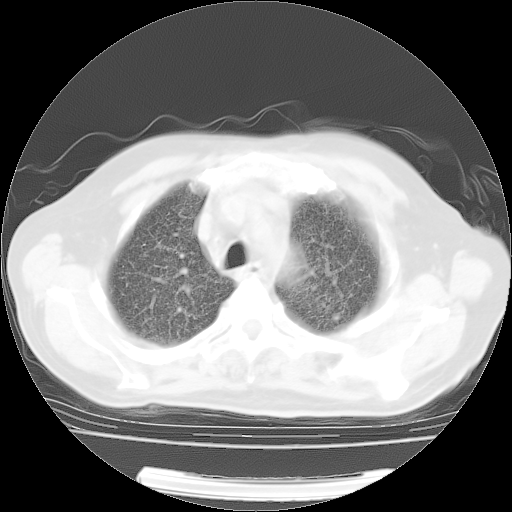

4月14日肺部CT

23.JPG

24.JPG

25.JPG

26.JPG

肺部CT平扫未见异常。